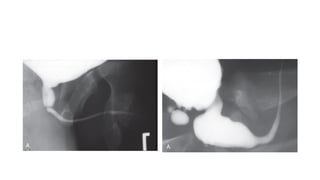

IVU aka Excretory Urography is a contrast radiograph of KUB

•Iodine contrast medium is given intra venously

•scout images

•nephrogram (1-2 minutes)

•early and late images of the upper collecting system (>3 minutes)

•supine images of the upper collecting system and proximal ureters

(10-15 minutes)

•Erect films may be taken for ureters

•Post void film

Retrograde Urography

•Rarely used after advent of ct scan

•Can be done if IVU and CT fail to visualise ureteral segment

•Involves ureteroscopy, hence access for simultaneous biopsy or

intervention is available